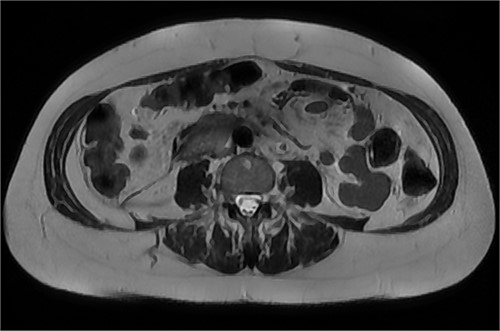

MRI abdomen, axial view. T2 hypointense, T1 iso to hyperintense material surrounding D2/D3 without enhancement in keeping with hemorrhage. No vascular or bowel wall lesion identified.

After further discussion with the reporting radiologist, a magnetic resonance imaging (MRI) was performed, which confirmed the presence of an acute periduodenal hematoma surrounding D2 and D3, lying in the retroperitoneal space, anterior to the right perirenal space. Etiology was uncertain. No abnormal enhancement within the bowel to suggest a bowel wall lesion or infiltrating mass (Figs 3 and 4).

MRI abdomen, coronal view. T2 hypointense, T1 iso to hyperintense material surrounding D2/D3 without enhancement in keeping with hemorrhage. No vascular or bowel wall lesion identified.